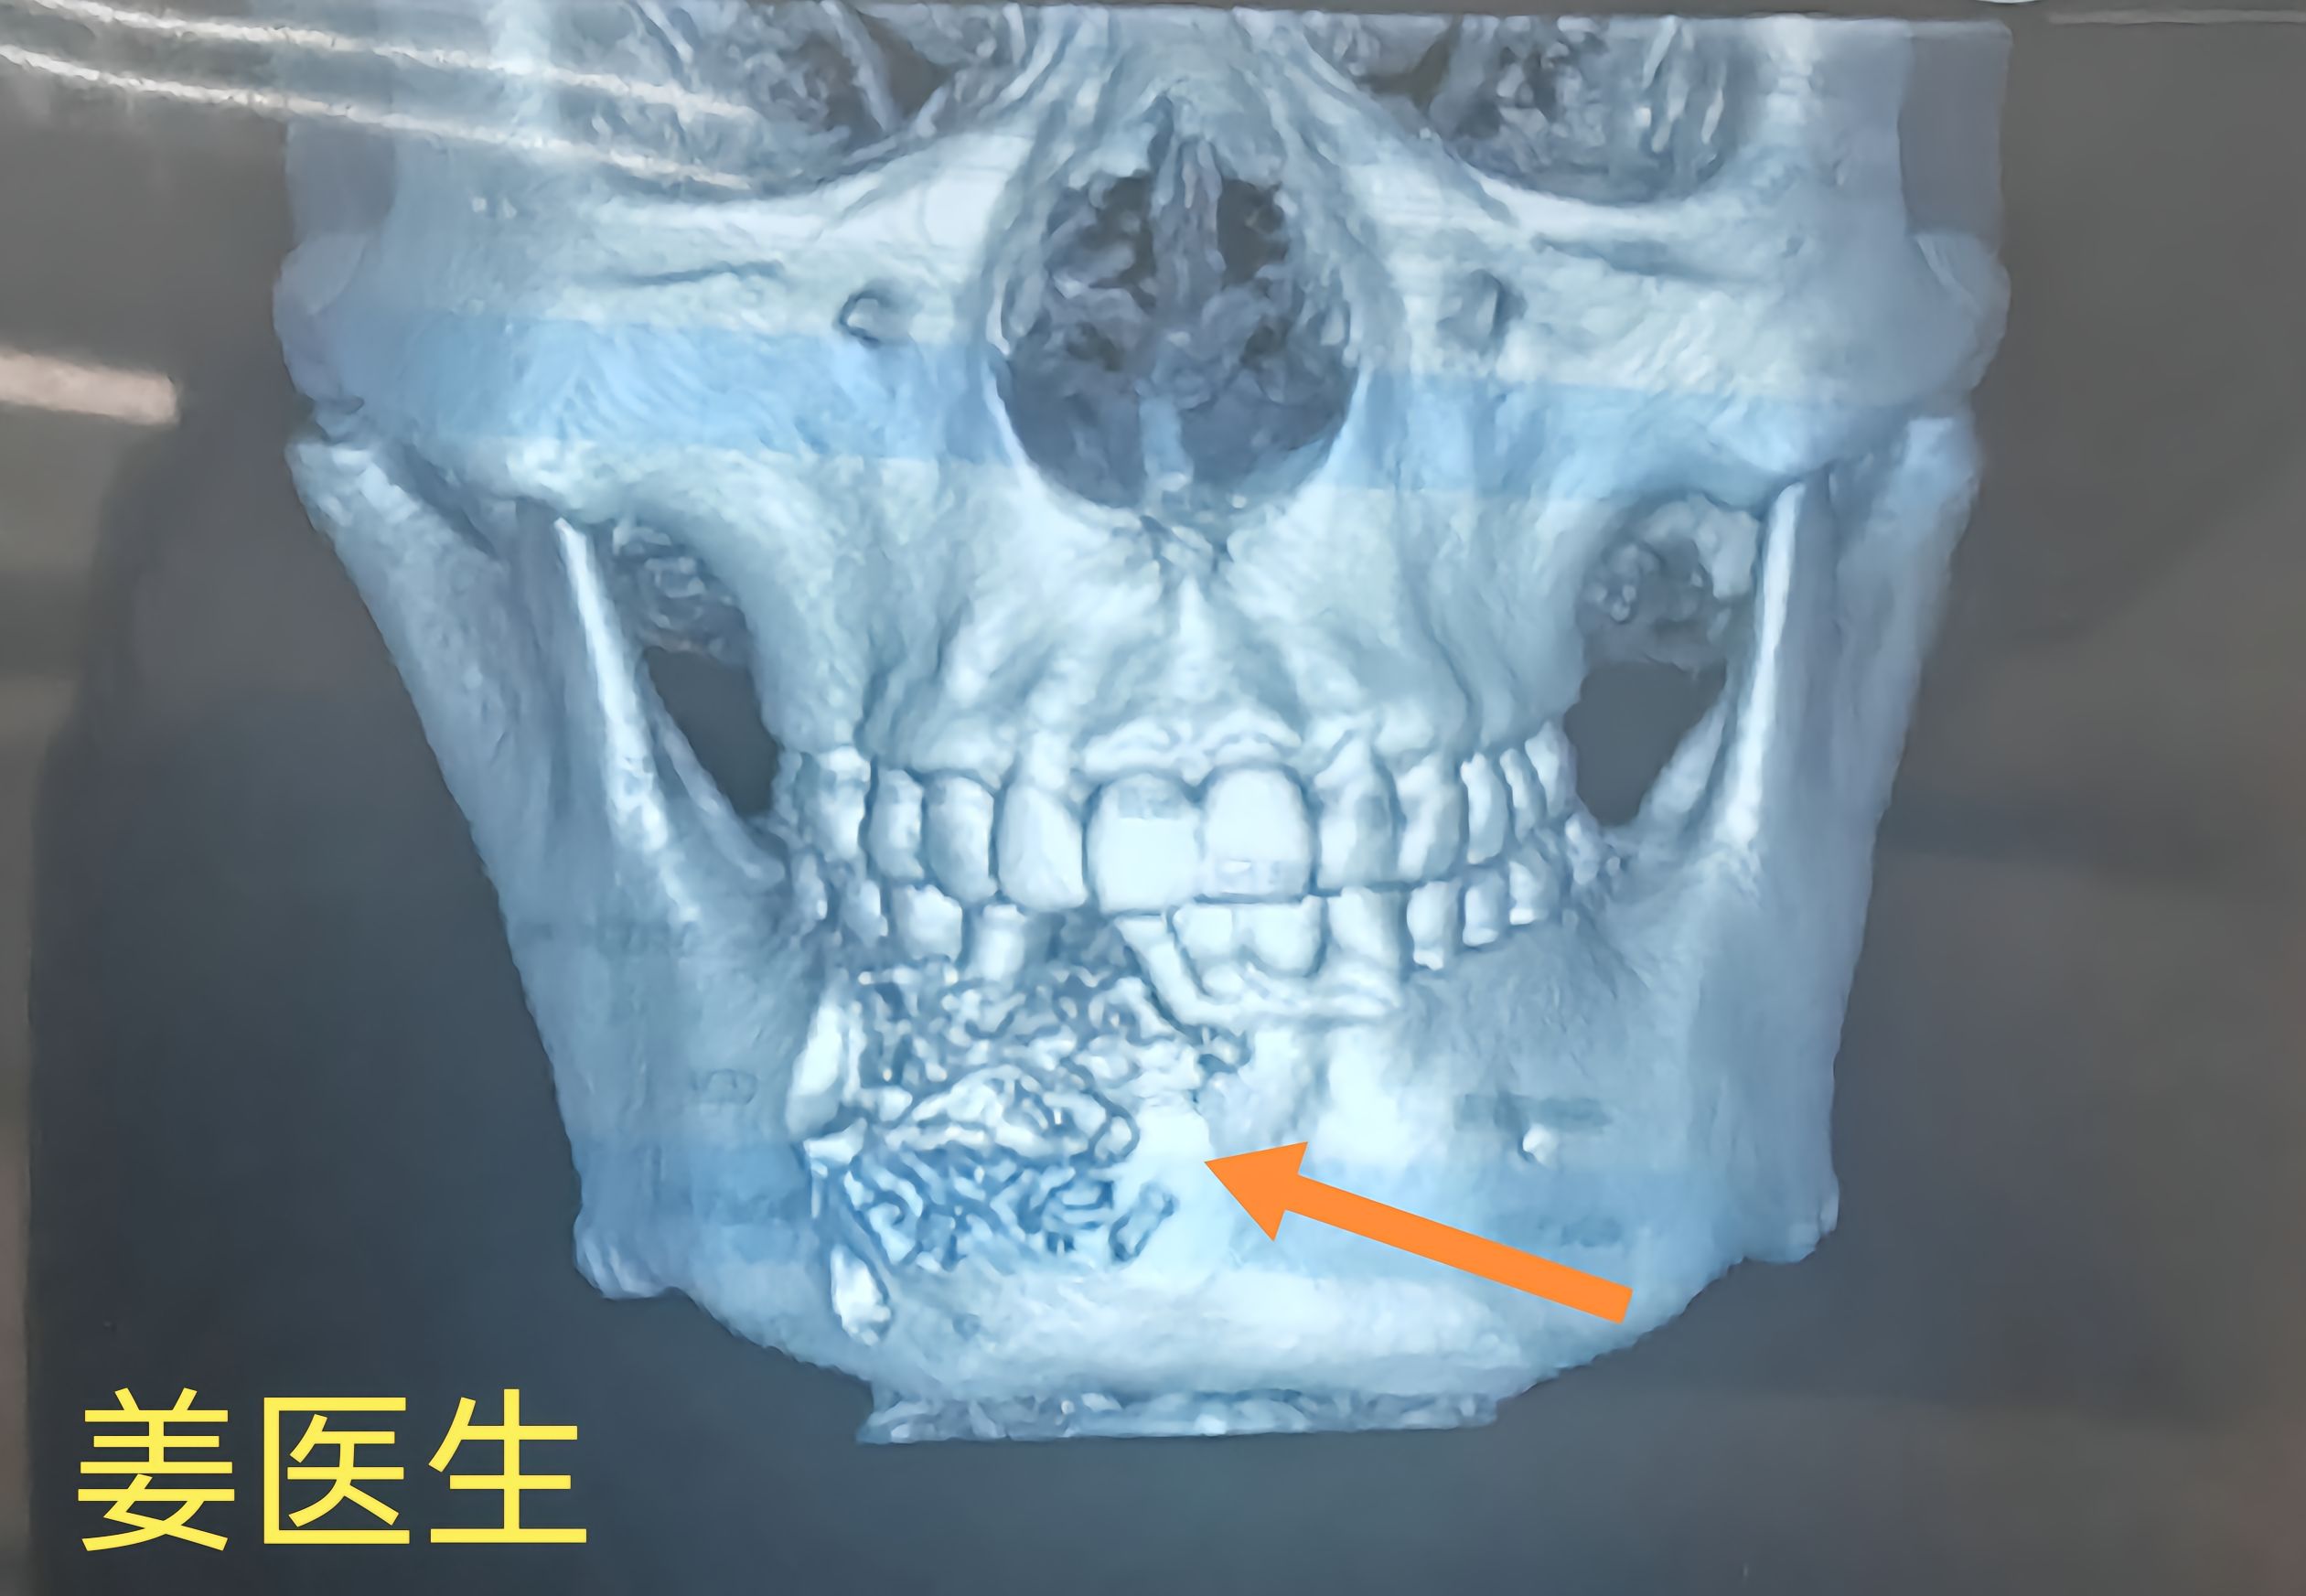

骨纤维异常增殖症

大量异常纤维组织或不成熟编织骨代替

了正常的骨组织